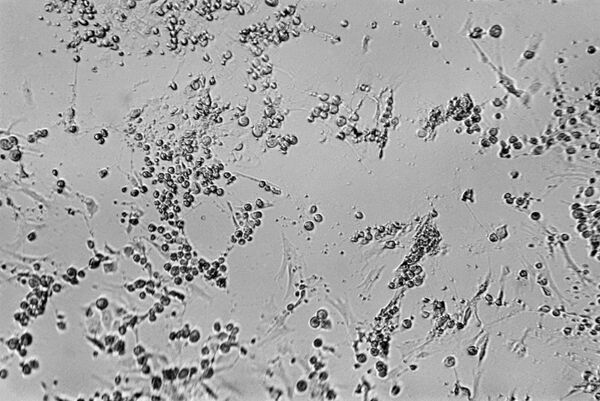

天然痘は伝染力の強い感染症で、発熱、皮膚や粘膜への発疹、重篤な経過などを特徴とし、回復後は痘痕が残ることもしばしばあり、死に至ることもある。